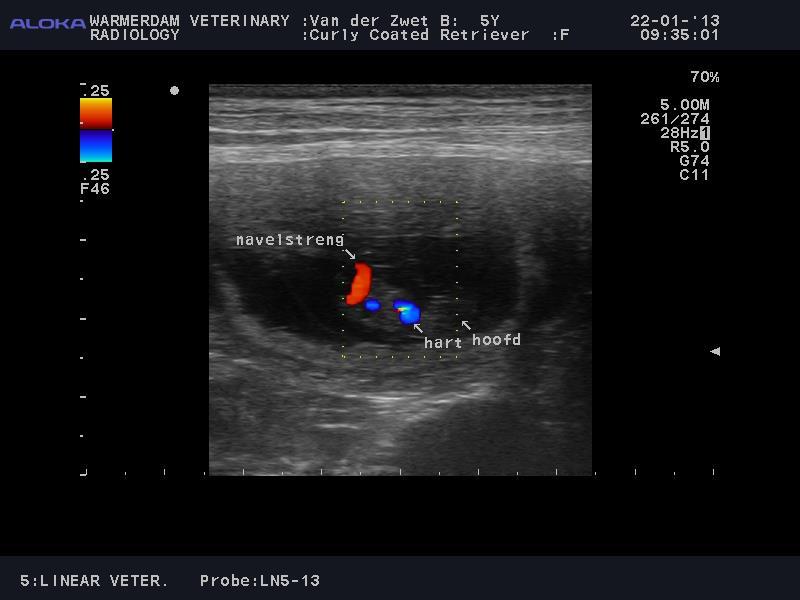

Litter Cody and Blom!

Blom (Uved's Sweetie Zitrus) almost 7 weeks pregnant.